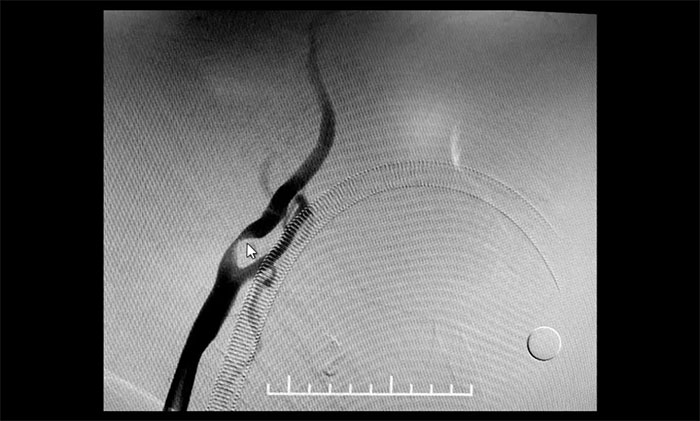

▲ 于耀宇主任为患者做DSA检查

颈内动脉狭窄可分为轻度(<50%),中度(50%~69%)和重度(70%~99%),椎动脉狭窄的判别标准与之相仿。DSA检查示:患者双侧颈内动脉及左侧椎动脉存在重度狭窄,狭窄程度达到甚至超过90%,病情十分严重,遂立即收治入院。

▲ 双侧颈内动脉及左侧椎动脉重度狭窄